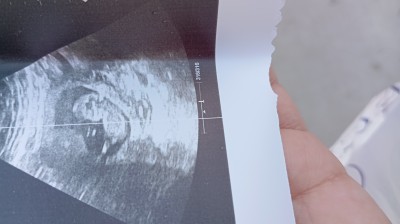

11+3 ultrason goruntusu

Gebelik haftası 11+3